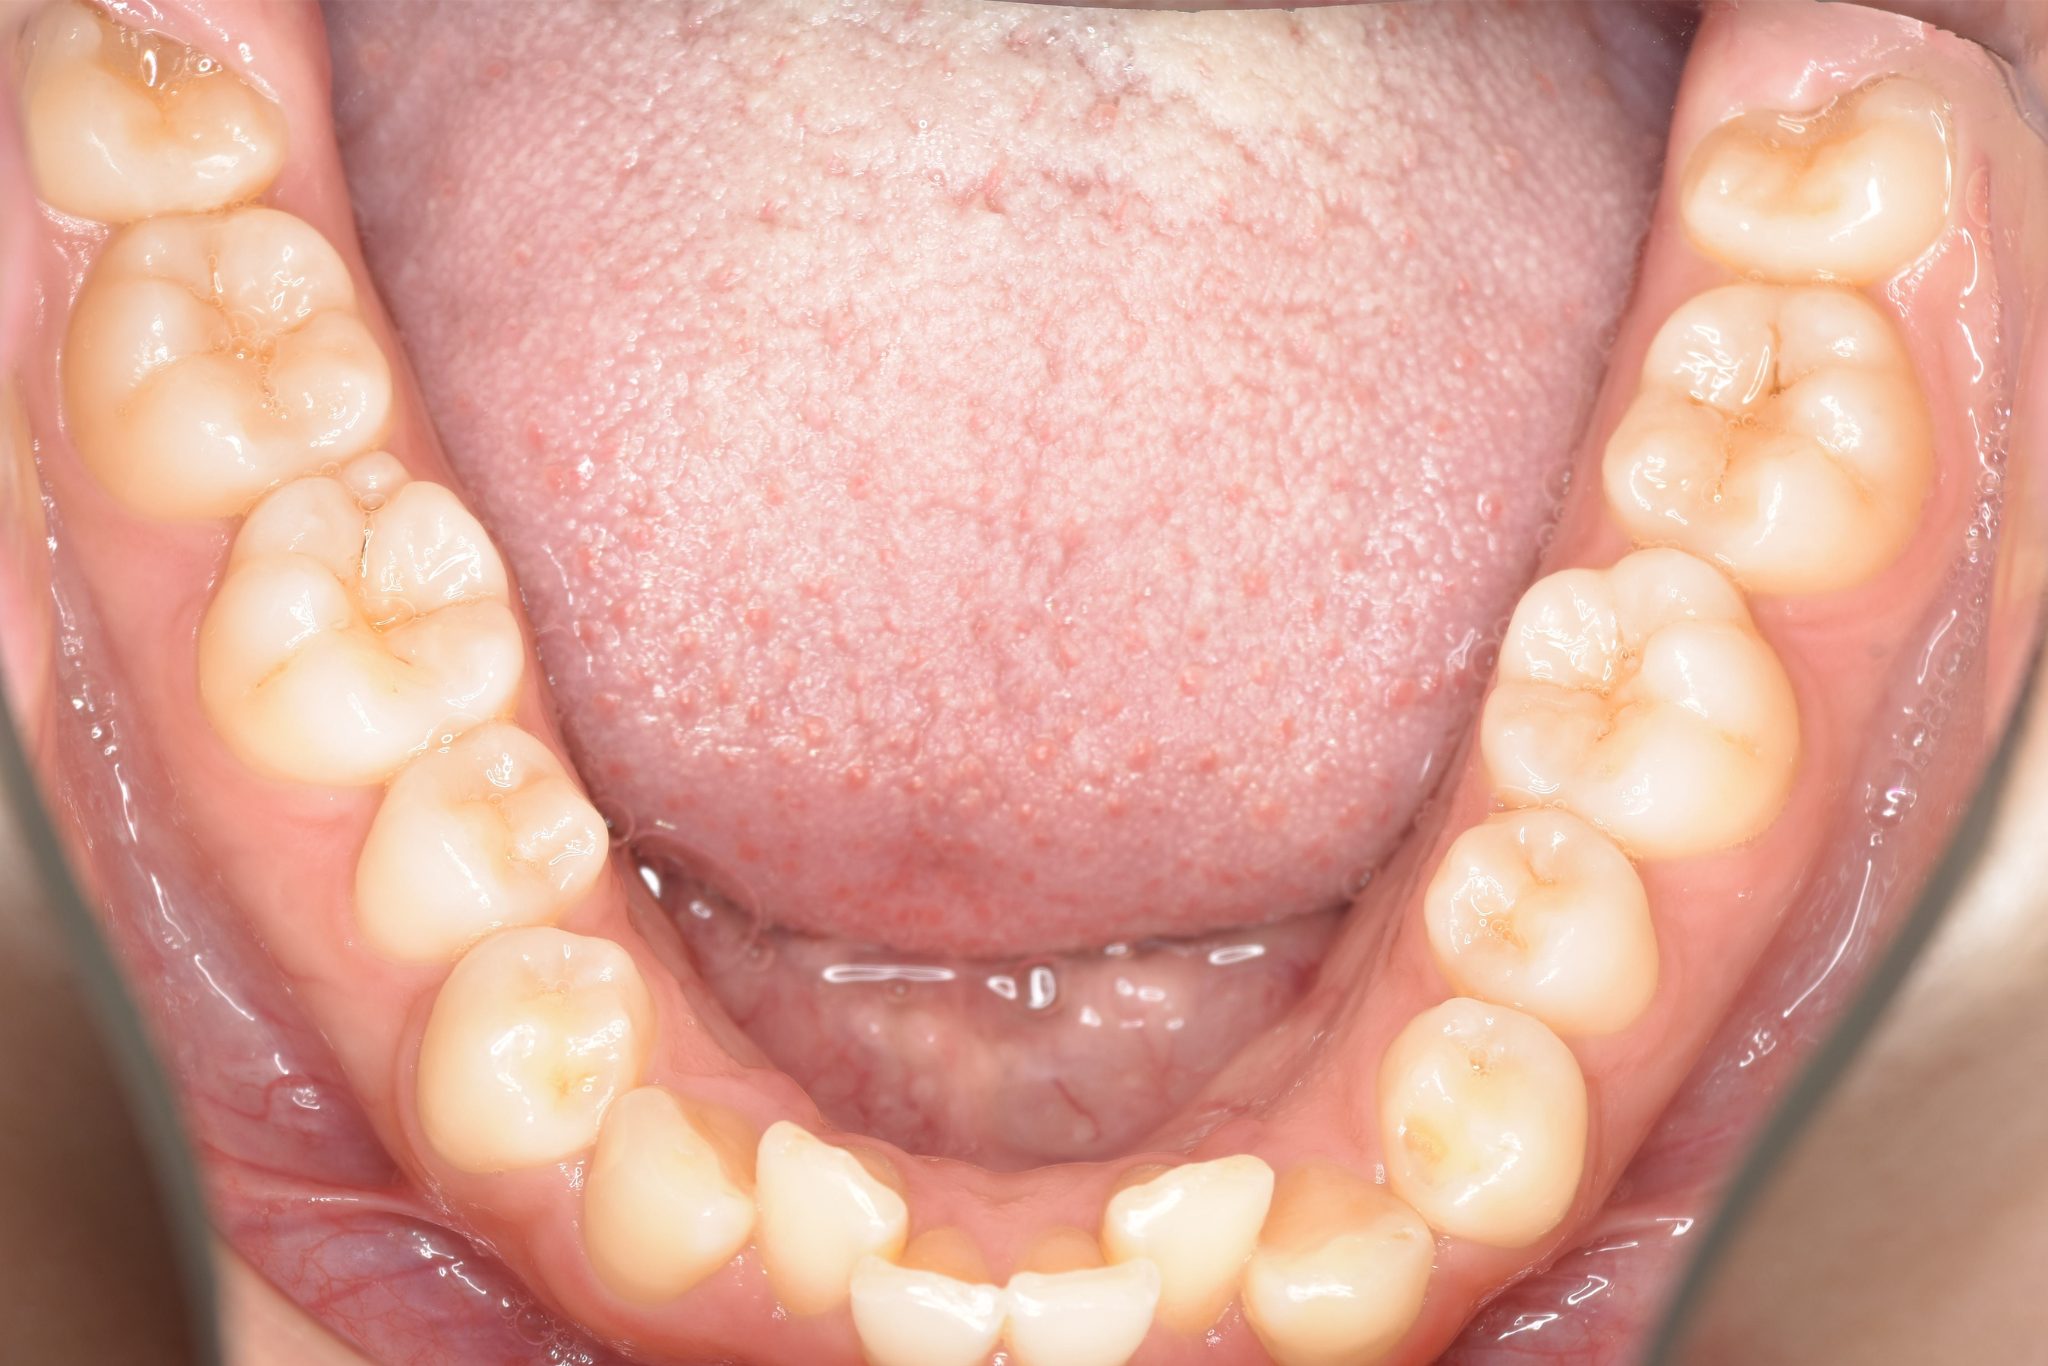

ビフォー

インビザライン矯正治療|症例_315

主訴 食べ物を前歯で噛み切れない|上顎の右側の歯が重なっている|下の歯がガタガタ

施術内容 MSEと下顎リンガルアーチを用いて上下顎骨を拡大した。

その後アライナー型矯正装置(インビザライン)を用いて非抜歯で歯牙を配列した。